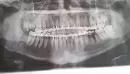

Сломал челюсть, сделали шинирование неделю назад. Оцените проблему и когда можно снять шинирование?

Комментарий №173256

• Двусторонний перелом нижней челюсти. Репозицию отломков проводят сроком не менее одного месяца.